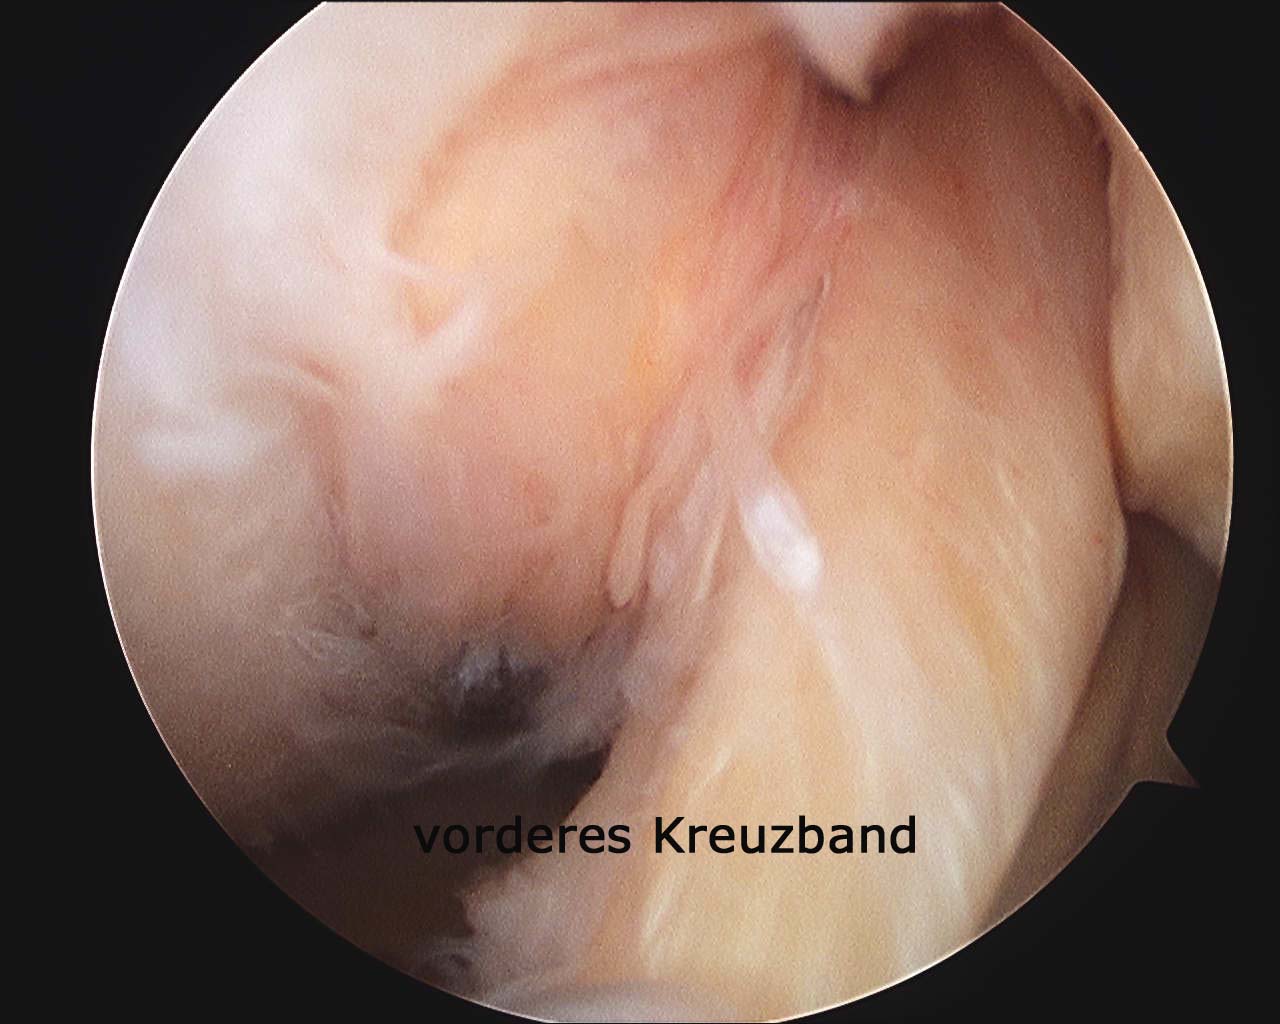

Arthroskopie

Bild anklicken zum Vergrössern

Bei Nichtansprechen der konservativen Therapiemaßnahmen können in Fällen mit noch geringer radiologischer Veränderung und guter  Beweglichkeit  der betroffenen Gelenke weitere, dann jedoch invasiver Maßnahmen zur Therapie erforderlich sein.  So kann sowohl bei Hüfte als auch Kniegelenk eine arthroskopische Operation – also ein wenig invasiver Eingriff – die Schmerzen dauerhaft lindern.